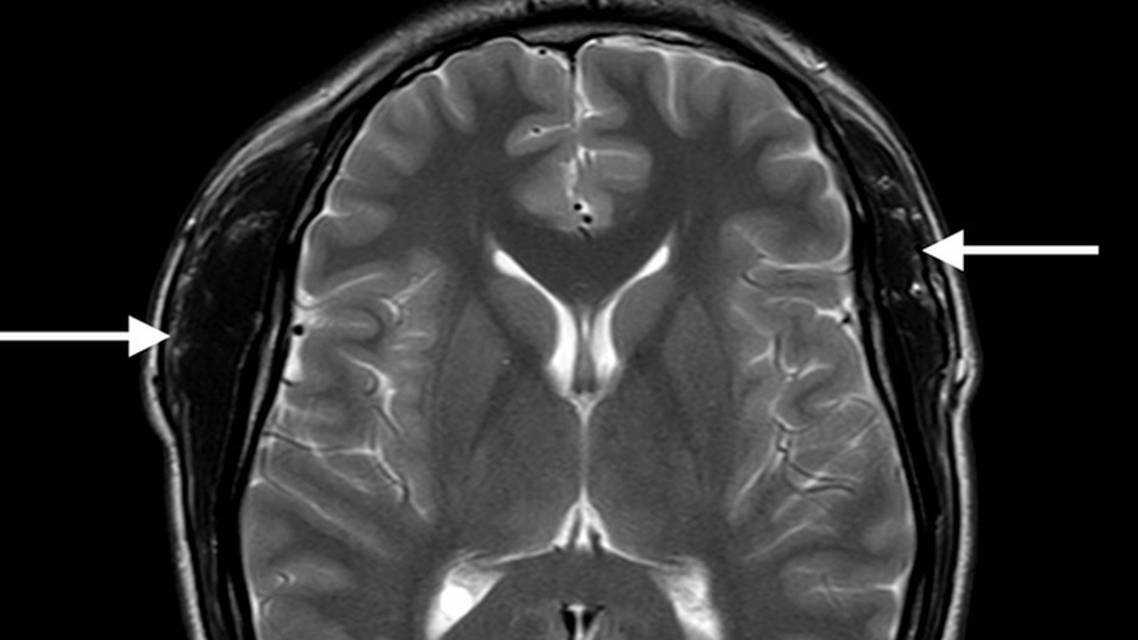

Inflammatory markers, myopathic screen, anti-muscle-specific receptor tyrosine kinase (MuSK) antibodies, and paraneoplastic screen were negative or within normal range. MRI of the head showed diffuse hypertrophy of the temporalis muscles bilaterally with no bony abnormalities (Figure 2). Biopsy of the right temporalis muscle showed mostly normal muscle but there were some focally enlarged fibers with internal nuclei as well as focal fatty and fibrous replacement of the muscle. These were nonspecific changes that reflected a reaction to chronic damage. There were no biopsy features to suggest inflammatory myopathy or vascular malformation. Based on the MRI and biopsy results, a diagnosis of nonspecific muscle hypertrophy was made.

Figure 2. Fast field echo (A), axial T2 (B), and coronal fluid-attenuated inversion recovery (C) MRI scans of the brain showing diffuse hypertrophy of the temporalis muscles bilaterally (right > left).